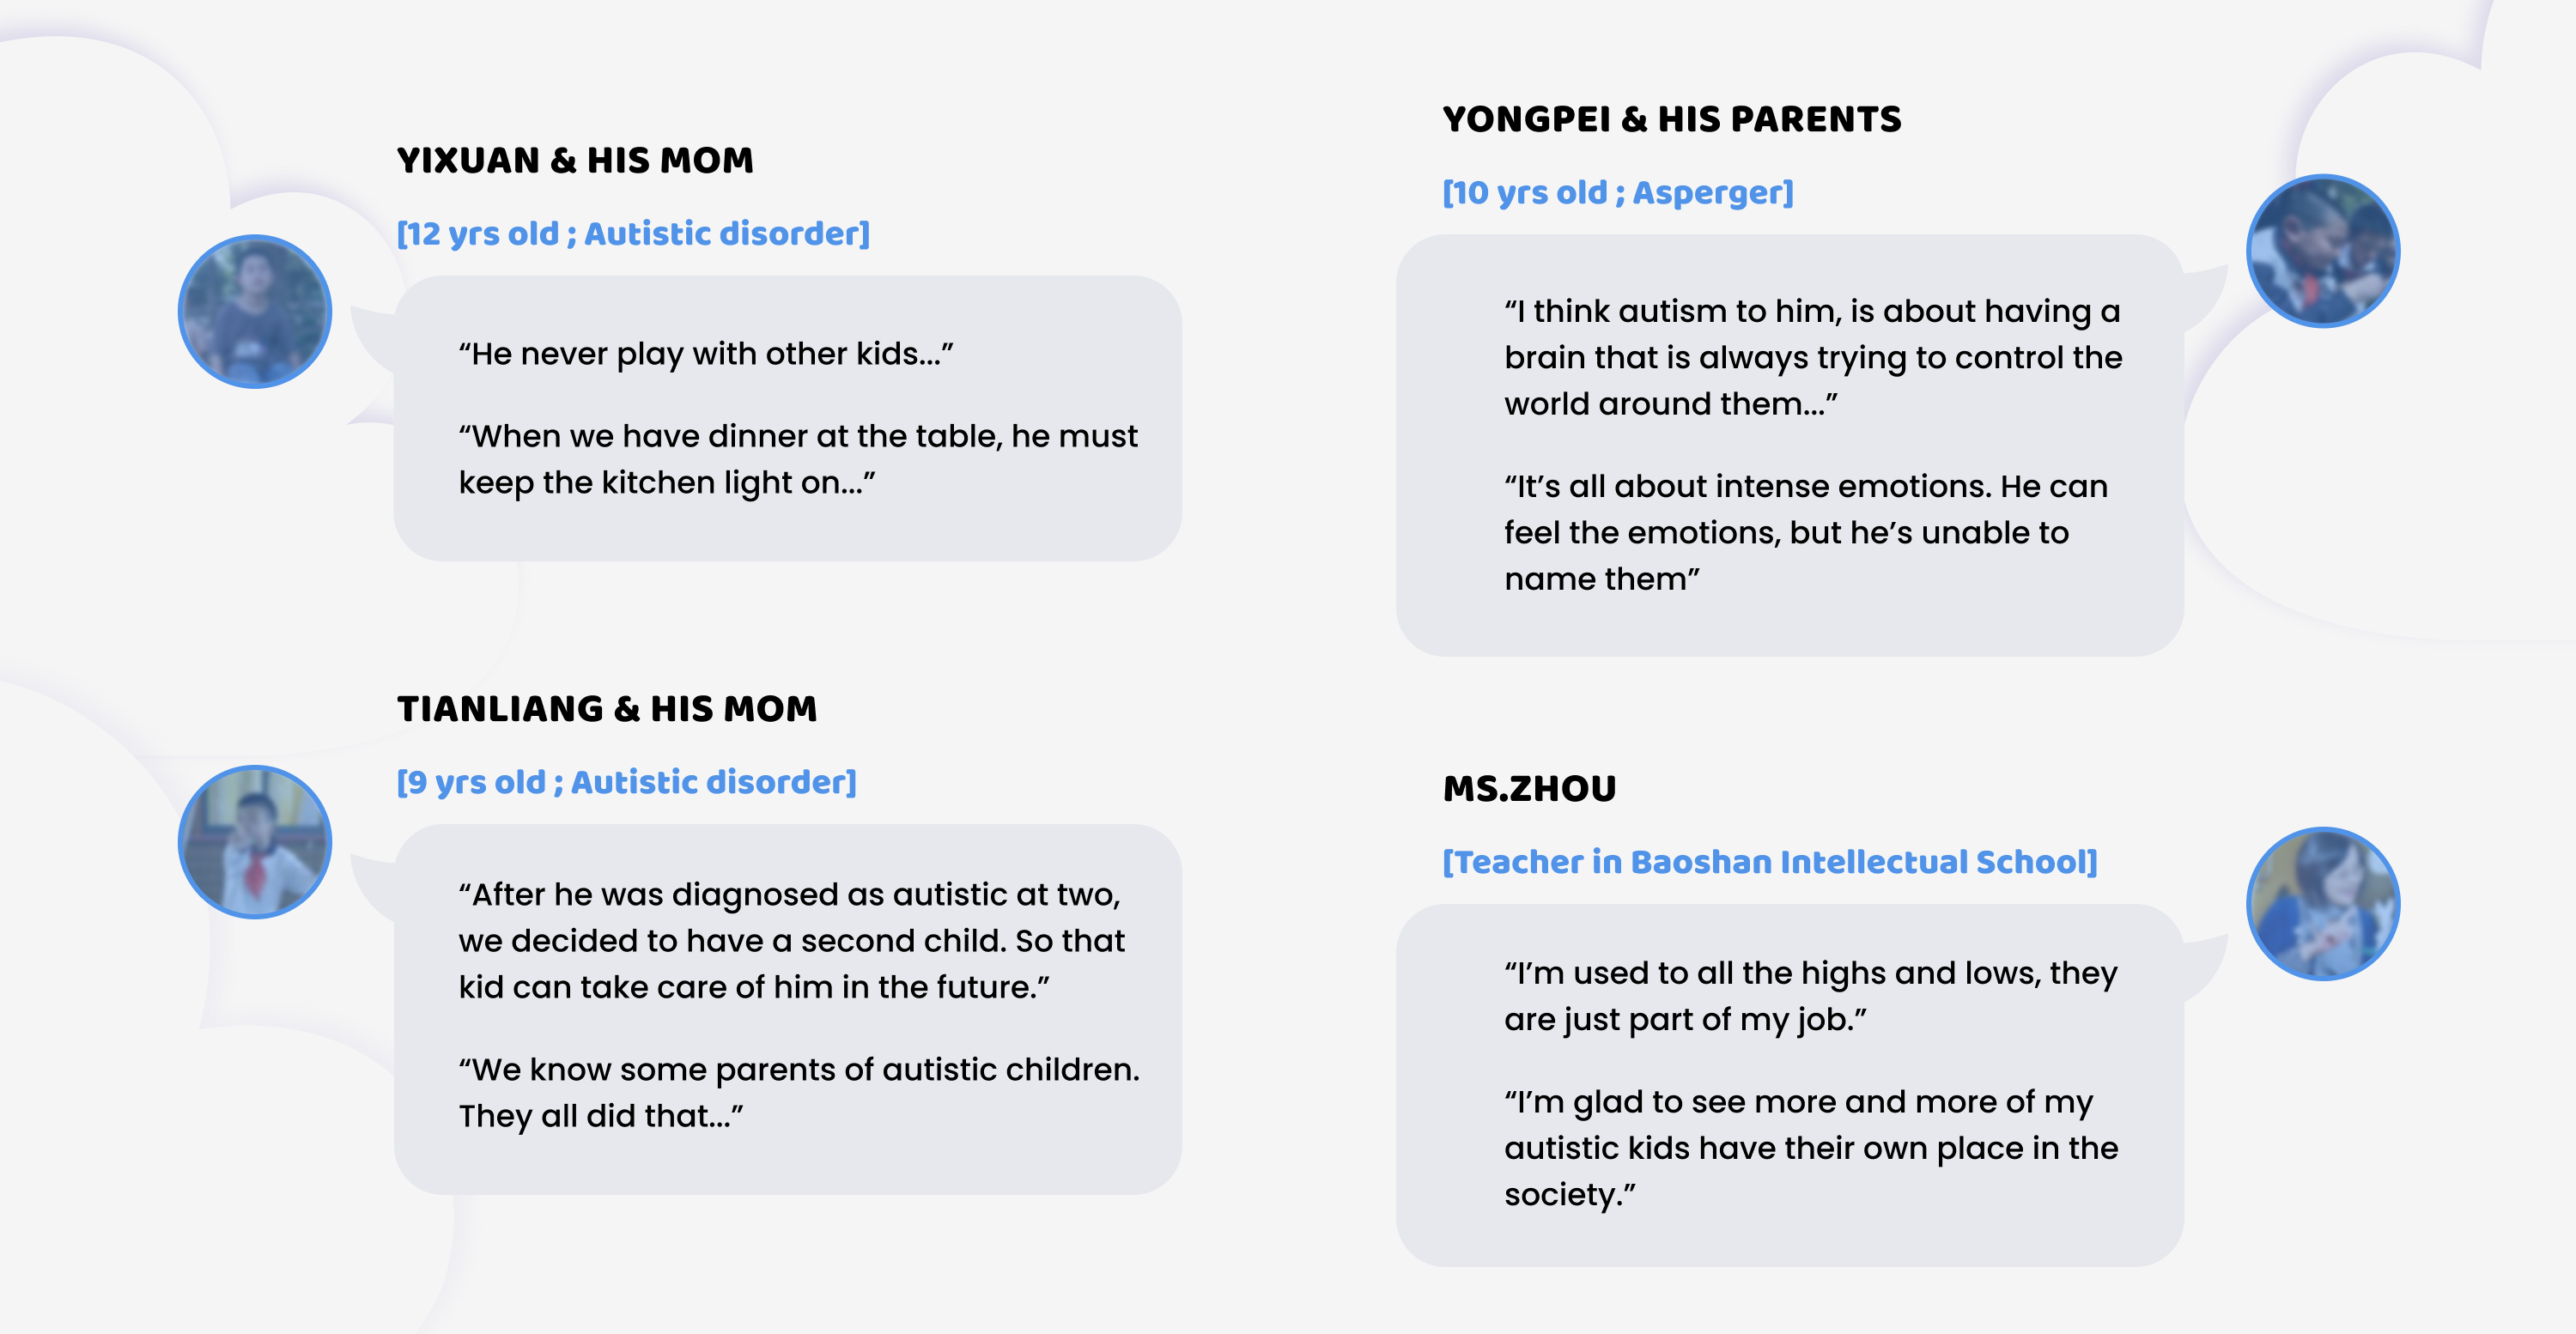

3. Coping with Anxiety and intense emotions 1 is a big challenge for most autistic people. Some of them can feel the emotion but has difficulties naming them, and some of them have hyper sensitivity to stimuli.

I went to Baozhan Intellectual School, which serves children with all kinds of mental and intellectual disabilities. I talked to 3 autistic kids and their parents, and their mentor Miss Zhou. I brought a box of colored markers, and gave a creative task to them. I intended to test their ability to concentrate.

However, I found they were more interested in the arrangement of colored markers than drawing. Some of them carefully arranged the markers in the order they wanted, which is a super interesting finding that proves autistic people have pattern seeking behavior.